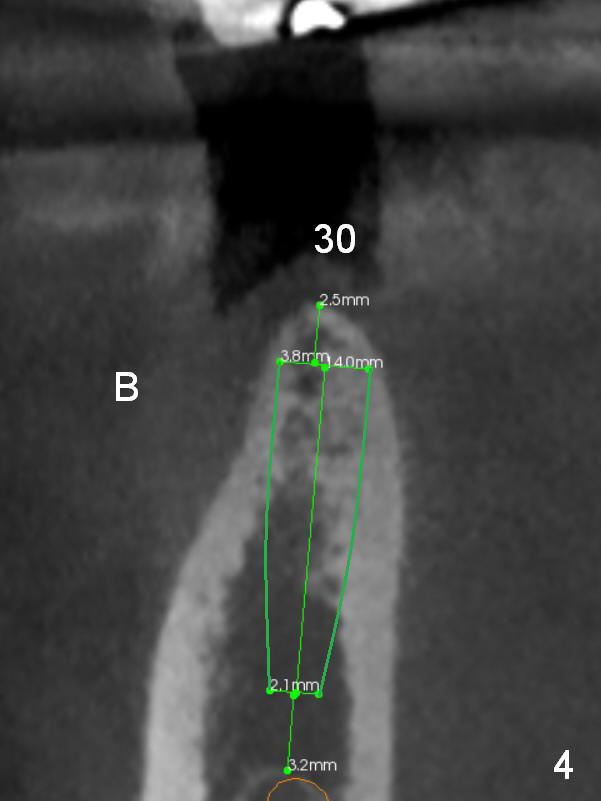

The narrow ridge at #30 will be split with wheel saw; osteotomy will be finished using bone expanders (Fig.4).